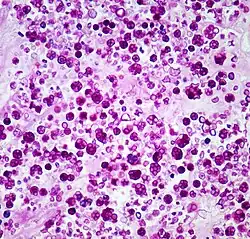

| Histologic stain of a Prototheca zopfii infection in a dog | |